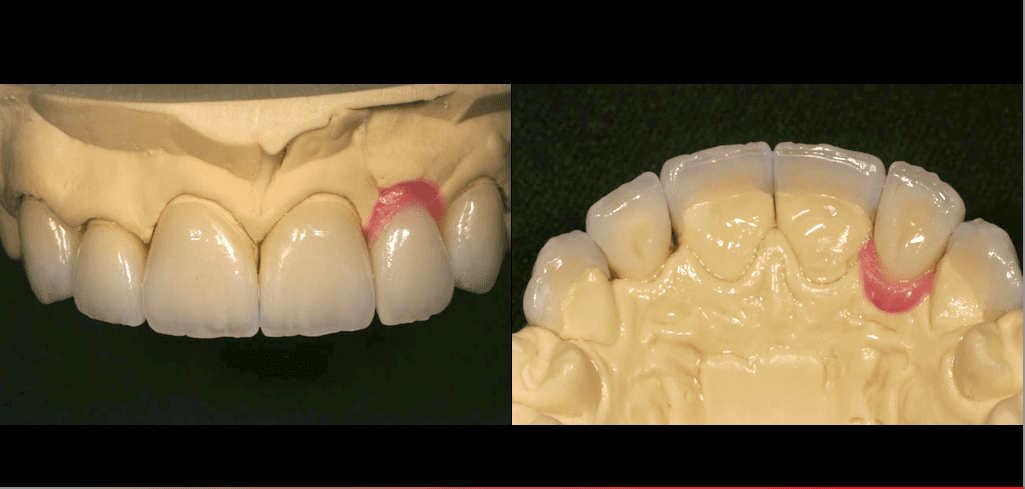

La reconstruction dentaire a été réalisée en combinant des implants dentaires, des facettes en porcelaine et des couronnes.

La reconstruction des dents avant et après montre la procédure de laboratoire pour les implants dentaires, la mise en place de gencives roses, pour corriger la longueur de la dent, la préparation pour les facettes en porcelaine, en combinaison avec une couronne dentaire, le tout assorti à la couleur pour avoir un sourire naturel agréable.